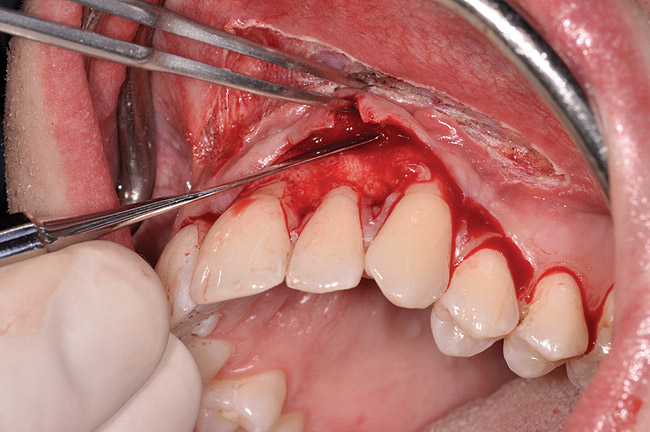

Fig 3. Example of laser-assisted split-thickness

vestibuloplasty.

Figure 3

The authors have introduced a laser-assisted vestibuloplasty approach (LAVA) procedure that is designed to prevent recurrent recession after surgical correction, which has been reported in the literature.29,38 This first involves a flap procedure for insertion of the dermal matrix graft material to be used to achieve root coverage and increase zones of existing attached keratinized tissues. To complete the vestibuloplasty procedure, the surgeon separates the mucosal tissues apical to the preexisting mucogingival junction in the area of the teeth exhibiting gingival recession. The authors advocate using a Nd:Yag laser with a power setting at 5 watts to accomplish the vestibuloplasty and release any excessive muscle attachments or frenal pulls in the affected areas (Figure 3).

After initial incision techniques were done, a papillary-sparing incision was performed, leaving the crest of the papilla intact (Figure 10), thus allowing flap closure to be accomplished with a bed of autogenous tissue to support revascularization of the dermis/buccal flap complex. A full-thickness flap was then elevated to the mucogingival junction, after which a split-thickness dissection with a blunt elevator superior to the mucogingival junction area was performed to allow for release of tension and to let the buccal flap be mobilized coronally at closure (Figure 10). Care must be taken to avoid perforating the tissue in the region of the vestibuloplasty incision. After tension-free release of the flap, root planing of the exposed root surfaces was accomplished, followed by removal of the smear layer of cementum and chemical detoxification with a citric acid solution pH1 applied over the previously root-planed surfaces. After root preparation, the keratinized papillary tissues that remained following initial incisions were de-keratinized by using a #4 round diamond on a high-speed handpiece. De-keratinization provided a wound bed that enabled the dermal matrix graft to be secured and supported revascularization of the coronally repositioned buccal flap at closure.